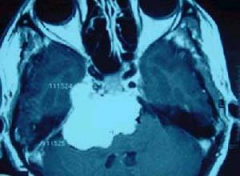

室管膜瘤(ependymoma)以青少年多见,约占颅内肿瘤的8%。男性多...

室管膜瘤是一种原发性肿瘤,这意味着它始于大脑或脊柱。大脑...